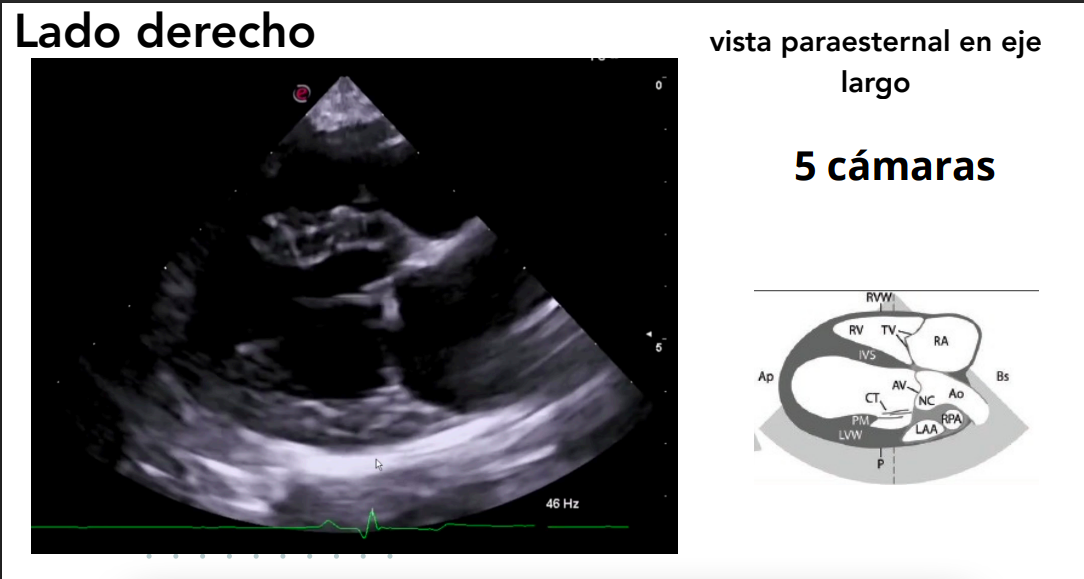

Vista paraesternal en eje largo

- 4 cámaras y 5 cámaras (incluye tracto de salida del VI).

- Evaluación de:

- Válvulas mitral, tricúspide y aórtica.

- Regurgitaciones valvulares.

- Defectos en septos interatrial e interventricular.